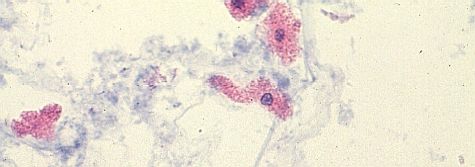

尿細管上皮細胞

ステルンハイマー変法染色円柱内の上皮細胞と同じ細胞が円柱外に散見される。

ステルンハイマー変法染色